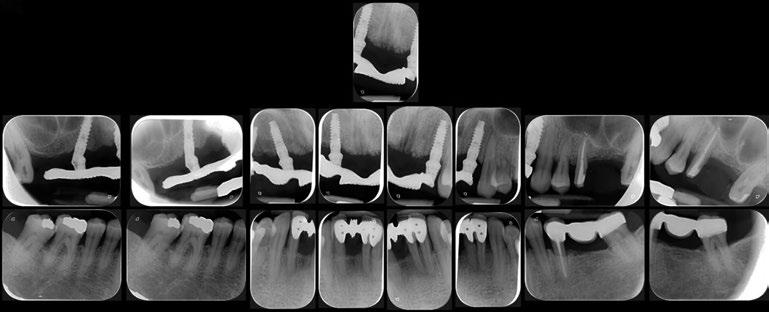

Radiografías intraorales iniciales.

Radiografías finales de la arcada superior.

Una vez ajustada la oclusión eliminando por completo todos los contactos céntricos y excéntricos y explicando los cuidados postoperatorios tanto sistémicos como locales, se finaliza la cirugía. En el control radiográfico 2D y 3D se puede evidenciar la correcta colocación del material de regeneración y el ajuste de la prótesis provisional (Figura 11).

Radiográficamente el perfil óseo es estable en la proyección 2D (Figuras 12, 13 y 14).